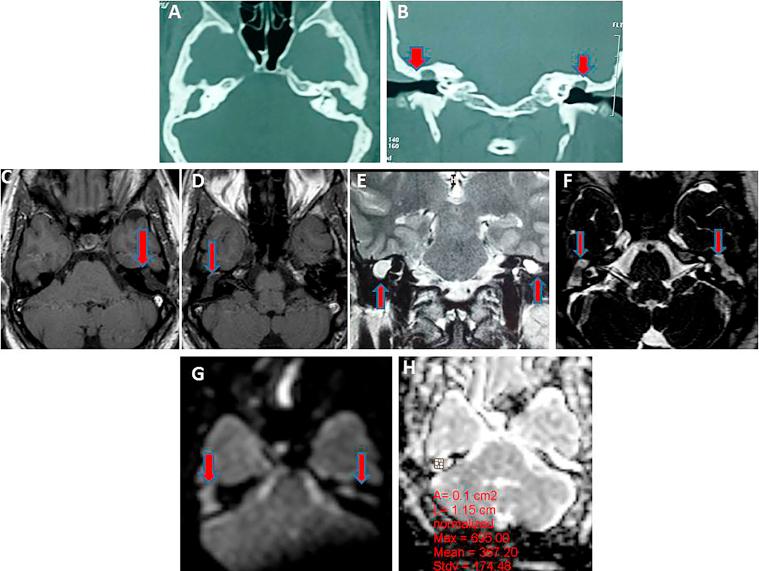

CT showed partial opacification of the tympanomastoid cavity in 10 ears and complete opacification in 21 ears. CT detects 10 cases out of 20 cases of recurrent cholesteatoma with sensitivity 47.6%, specificity 100%, and NPP 47.6%. DWI depicted 21 out of 20 cases proved cholesteatoma patients (sensitivity 100%, specificity 90%, PPV 95.2% and P value is 0.001). All MRI of patients without cholesteatoma were correctly interpreted as showing negative findings for cholesteatoma (specificity = 100%). The ADC of cholesteatoma group (21 ears) were ranged from 553 to 759 × 10 mm/s and the ADCs of non cholesteatoma group (10 ears) was ranged from 1495.8 to 1766.8 × 10 mm/s. Cut off value of cholesteatoma is ≤759 × 10 mm/s.

CT显示鼓室乳突腔部分混浊10耳,完全混浊21耳。CT在20例复发性胆脂瘤中检测出10例,敏感性为47.6%,特异性为100%,阴性预测值为47.6%。DWI在20例经证实的胆脂瘤患者中显示出21例(敏感性100%,特异性90%,阳性预测值95.2%,P值为0.001)。所有无胆脂瘤患者的MRI均被正确解读为胆脂瘤阴性结果(特异性 = 100%)。胆脂瘤组(21耳)的ADC值范围为553至759×10⁻⁶mm²/s,非胆脂瘤组(10耳)的ADC值范围为1495.8至1766.8×10⁻⁶mm²/s。胆脂瘤的截断值为≤759×10⁻⁶mm²/s。